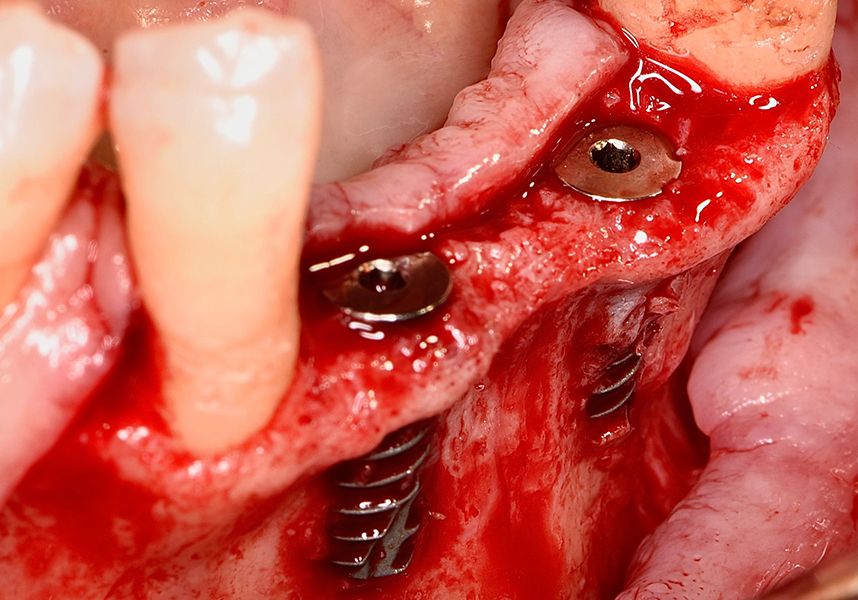

To treat the defect, bone regeneration was carried out simultaneous to the surgical process, with an autologous bone graft from the patient. In the internal part of the graft we used autologous cortical bone obtained by scraping (Safescraper) and from the biological drilling, at low revolutions and without irrigation, from the other implant beds. In the external layer of the regeneration we used a xenograft (Genoss, Osteogenos) and this was covered with a reabsorbable collagen barrier membrane (Evolution STD, Osteogenos).

The membrane was sutured with PGA reabsorbable suture to the periosteum to secure it, thus avoiding subsequent reentry to remove fixings such as tacks.

In the posterior sector three Biomimetic Ocean IC implants of 4.0x10 were inserted in positions 36, 34 and 46 with delayed load. A small regeneration was also carried out with autologous bone in the implant in position 34, where there was no exposure, but the vestibular cortical was very fine after implant insertion.